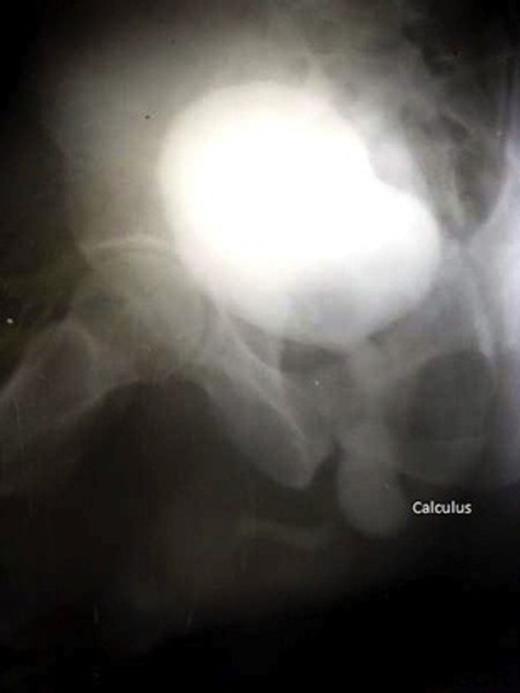

A 55 year male was admitted to our institution with complaints of pain and swelling in perineal region for 6 days and purulent discharge from the swelling for 2 days. Patient was apparently quite well 4 months prior when he noticed a progressive thinning of urinary stream along with dysuria and burning on micturition. Three months later the patient had an episode of retention of urine for which patient attended our outpatient department. A trocar suprapubic catheterisation (SPC) was performed and a 16 Fr Foley’s catheter was passed into the bladder. Patient was asymptomatic for 1 month followed by reappearance of the swelling and pain in the perineal region. On local examination there was a swelling 2 x 2 cms in size in the left perineal region with purulent discharge. Urine culture and pus culture showed growth of Klebsiella resistant to all tested antimicrobials. Patient was subjected to retrograde urethography (figure 1) and micturiting cystourethography (figure 2). Patient was diagnosed as a case of urethral calculus with urethral stricture and was posted for urethral calculus removal with urethroplasty. The calculus of 30mm x 20mm x15mm (figure 3) was extracted successfully and end to end urethroplasty was performed.